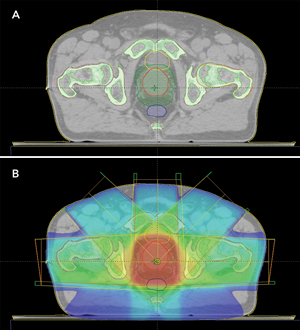

2 Conventional computed tomography scans for delineating the prostate and surrounding normal tissues, and calculating radiation dose

In EBRT for prostate cancer, high-energy x-ray beams from multiple directions deposit energy (dose) within the tumour (prostate) to destroy cancer cells. The standard process for EBRT treatment planning is shown in Box 1(A). The first step is patient imaging (a CT scan sometimes combined with MRI). The treatment targets (the prostate and sometimes the seminal vesicles) and important normal tissues (the rectum, bladder, and femoral heads) are then manually defined from the scans (Box 2). Modern radiotherapy machines offer improved treatment accuracy through better visualisation and the correction of errors in patient setup, making target delineation the most significant uncertainty in radiotherapy planning.

MRI scans have vastly superior soft-tissue contrast compared with CT scans, with better visualisation and more accurate delineation of the border of the prostate. Prostate borders delineated on MRI scans show greater consistency between radiation oncologists,5,6 and prostate size is smaller than that determined by CT scan.7 Using MRI, the size of the extra margins to be added to account for delineation uncertainties is reduced, and less normal tissue is irradiated, thus reducing treatment toxicity.